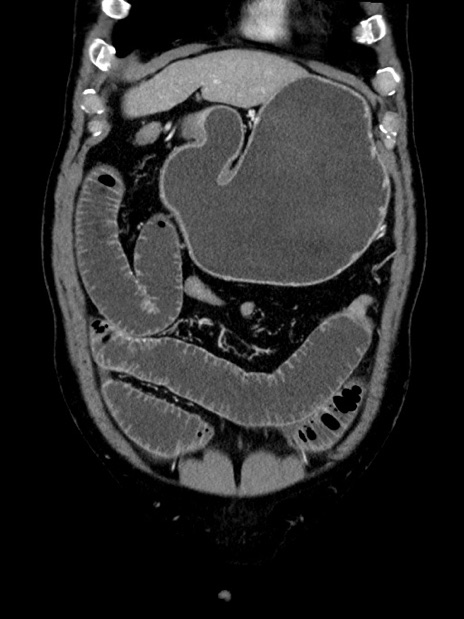

症例35(冠状断像)

【症例】70歳代 男性

【主訴】腹部膨満、嘔吐

【現病歴】昨日より腹部膨満感出現。本日増悪し、仙痛出現。嘔吐あり、受診。

【既往歴】糖尿病、胆摘後

【身体所見】BP 149/80mmHg、HR 74/min、BT 35.9℃、腹部:膨満、軟、圧痛なし。腸雑音減弱あり。上腹部正中切開瘢痕あり。

【データ】WBC 13500、CRP 1.72